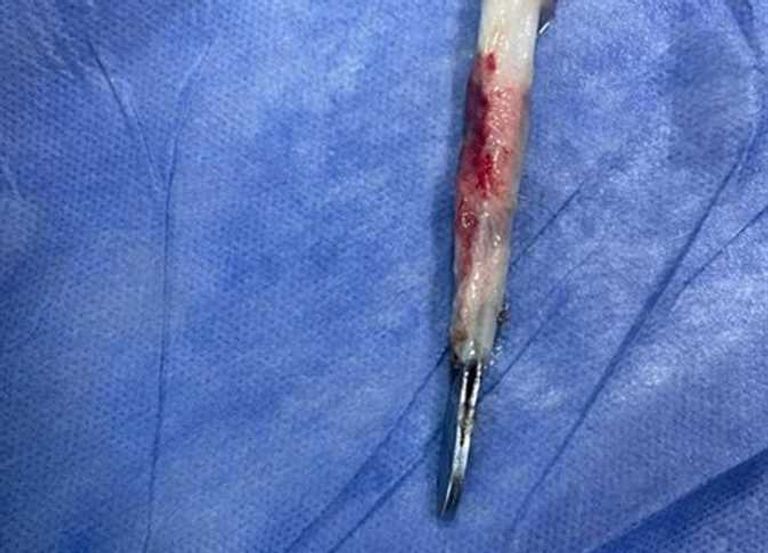

نجح فريق طبي في مستشفى بنها الجامعي بمحافظة القليوبية (دلتا مصر) في استخراج مِلقاط من القصبة الهوائية لمريض ابتلعه بالخطأ.

وأصدر مستشفى بنها بياناً كشف فيه تفاصيل الجراحة، وجاء فيه: "تمّ استخراج (مِلقاط شعر) من القصبة الهوائية لمريض يعاني من شق حنجري قديم".

وأضاف البيان: "المريض كان يقوم بتنظيف فتحة الشق الحنجري بطريقة غير صحيحة وغير طبية، عن طريق استخدامه ملقاط ملفوف بمناديل ورقية، وفوجئ بأن المِلقاط دخل إلى فتحة القصبة الهوائية".

وختم البيان: "نجح الدكتور باسم مفرح الأستاذ المساعد بالقسم، وبمعاونة الدكتور أحمد الخضري مدرس مساعد التخدير، من استخراج (الملقاط)، وخرج المريض من العمليات، ويخضع الآن للمتابعة لاستكمال علاجه بالقسم لحين تماثله الكامل للشفاء".